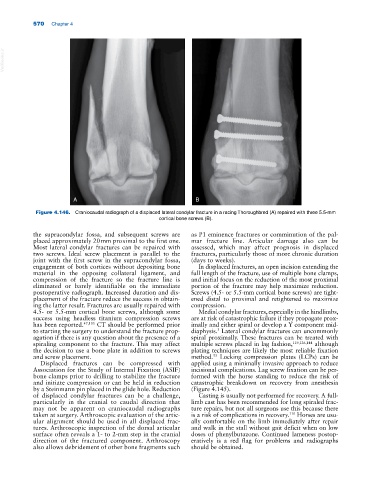

Figure 4.146. Craniocaudal radiograph of a displaced lateral condylar fracture in a racing Thoroughbred (A) repaired with three 5.5‐mm

cortical bone screws (B).